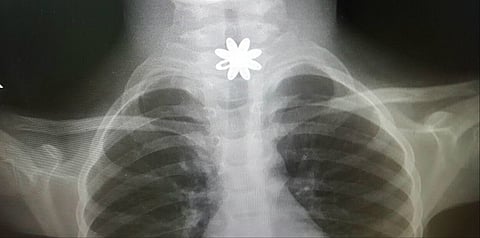

وكانت الطفلة قد أدخلت المستشفى وهي تعاني انسداداً بالمريء، وبعد تشخيص الحالة اتضح وجود قطعة معدنية حادة تشكل خطورةً على حياتها؛ ما أدّى إلى جروح قطعية داخل المريء؛ حيث خضعت الطفلة لعملية باستخدام منظار المريء الصلب لاستخراج القطعة المعدنية في وقتٍ قياسي، وبشكلٍ دقيق وسريع ومعالجة الحالة، لحين أن غادرت المستشفى بصحةٍ جيدة.

وأوضح المتحدث الرسمي لـ "صحة الطائف" عبدالهادي الربيعي؛ أن فريقاً طبياً مكوّناً من الدكتور إيهاب فوزى؛ والدكتور جاسر علي؛ استشاريي جراحة الصدر بالمجمع، والدكتور أحمد نصر؛ استشاري التخدير، نجحوا في إنقاذ حياة الطفلة - بعد توفيق الله -، مشيراً إلى أن مثل هذه العمليات كانت مقياساً لسرعة تعامل الفريق مع الحالة وإخضاعها للعملية بشكل فوري؛ نظرا للمخاطر المحتملة في زيادة مضاعفات الحالة، مقدماً شكره للفريق الطبي ومشيداً بهذا الإنجاز.